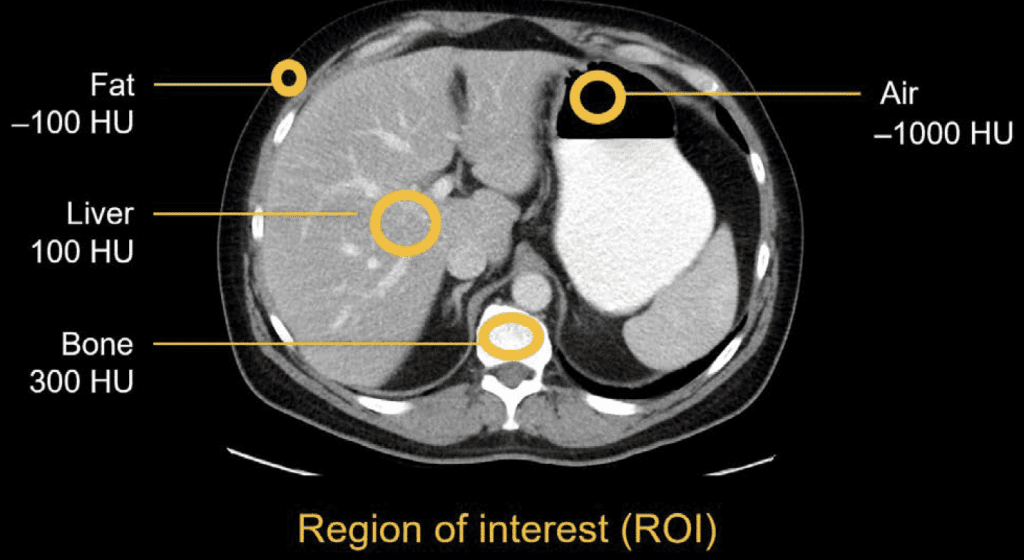

One important thing to remember when working with medical images is that not every image is “just a picture. Some modalities carry physical units in the pixels. CT (and in some cases X-ray) values are in Hounsfield Units (air ~= −1000, water ~= 0, cortical bone ~= 1000+). That can be extremely handy when you only need to look at specific structures in isolation, filtering the surrounding noise. X-ray intensities reflect path-length attenuation, so darker/brighter isn’t arbitrary contrast; it’s the beam’s journey through tissue and hardware. By contrast, MRI brightness is mostly relative; it depends on sequence, timing, and coil gain, which is why two “similar” scans can look different without anyone doing anything wrong. Ultrasound brings its own texture (speckle) and angle dependence. All of this matters for preprocessing and for what you let the model learn.